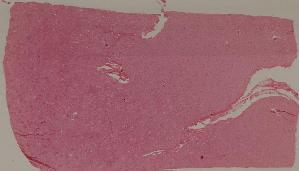

66. Active nodular cirrhosis of the liver

67. Inactive nodular cirrhosis of the liver

68. Biliary fibrosis

69. Hepatocellular carcinoma

72. Membranous glomerulonephritis

73. Acute glomerulonephritis

74. Crescentic glomerulonephritis

75. Chronic glomerulonephritis